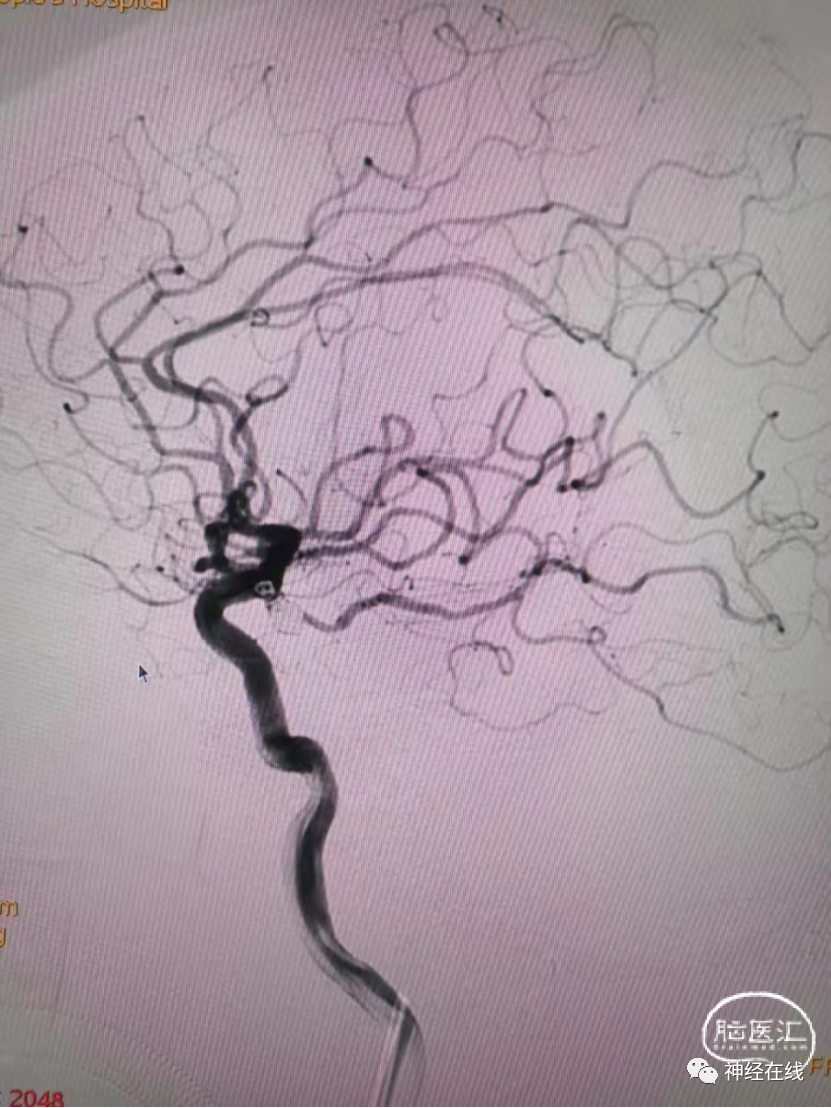

长条状破裂后交通动脉瘤弹簧圈栓塞病例